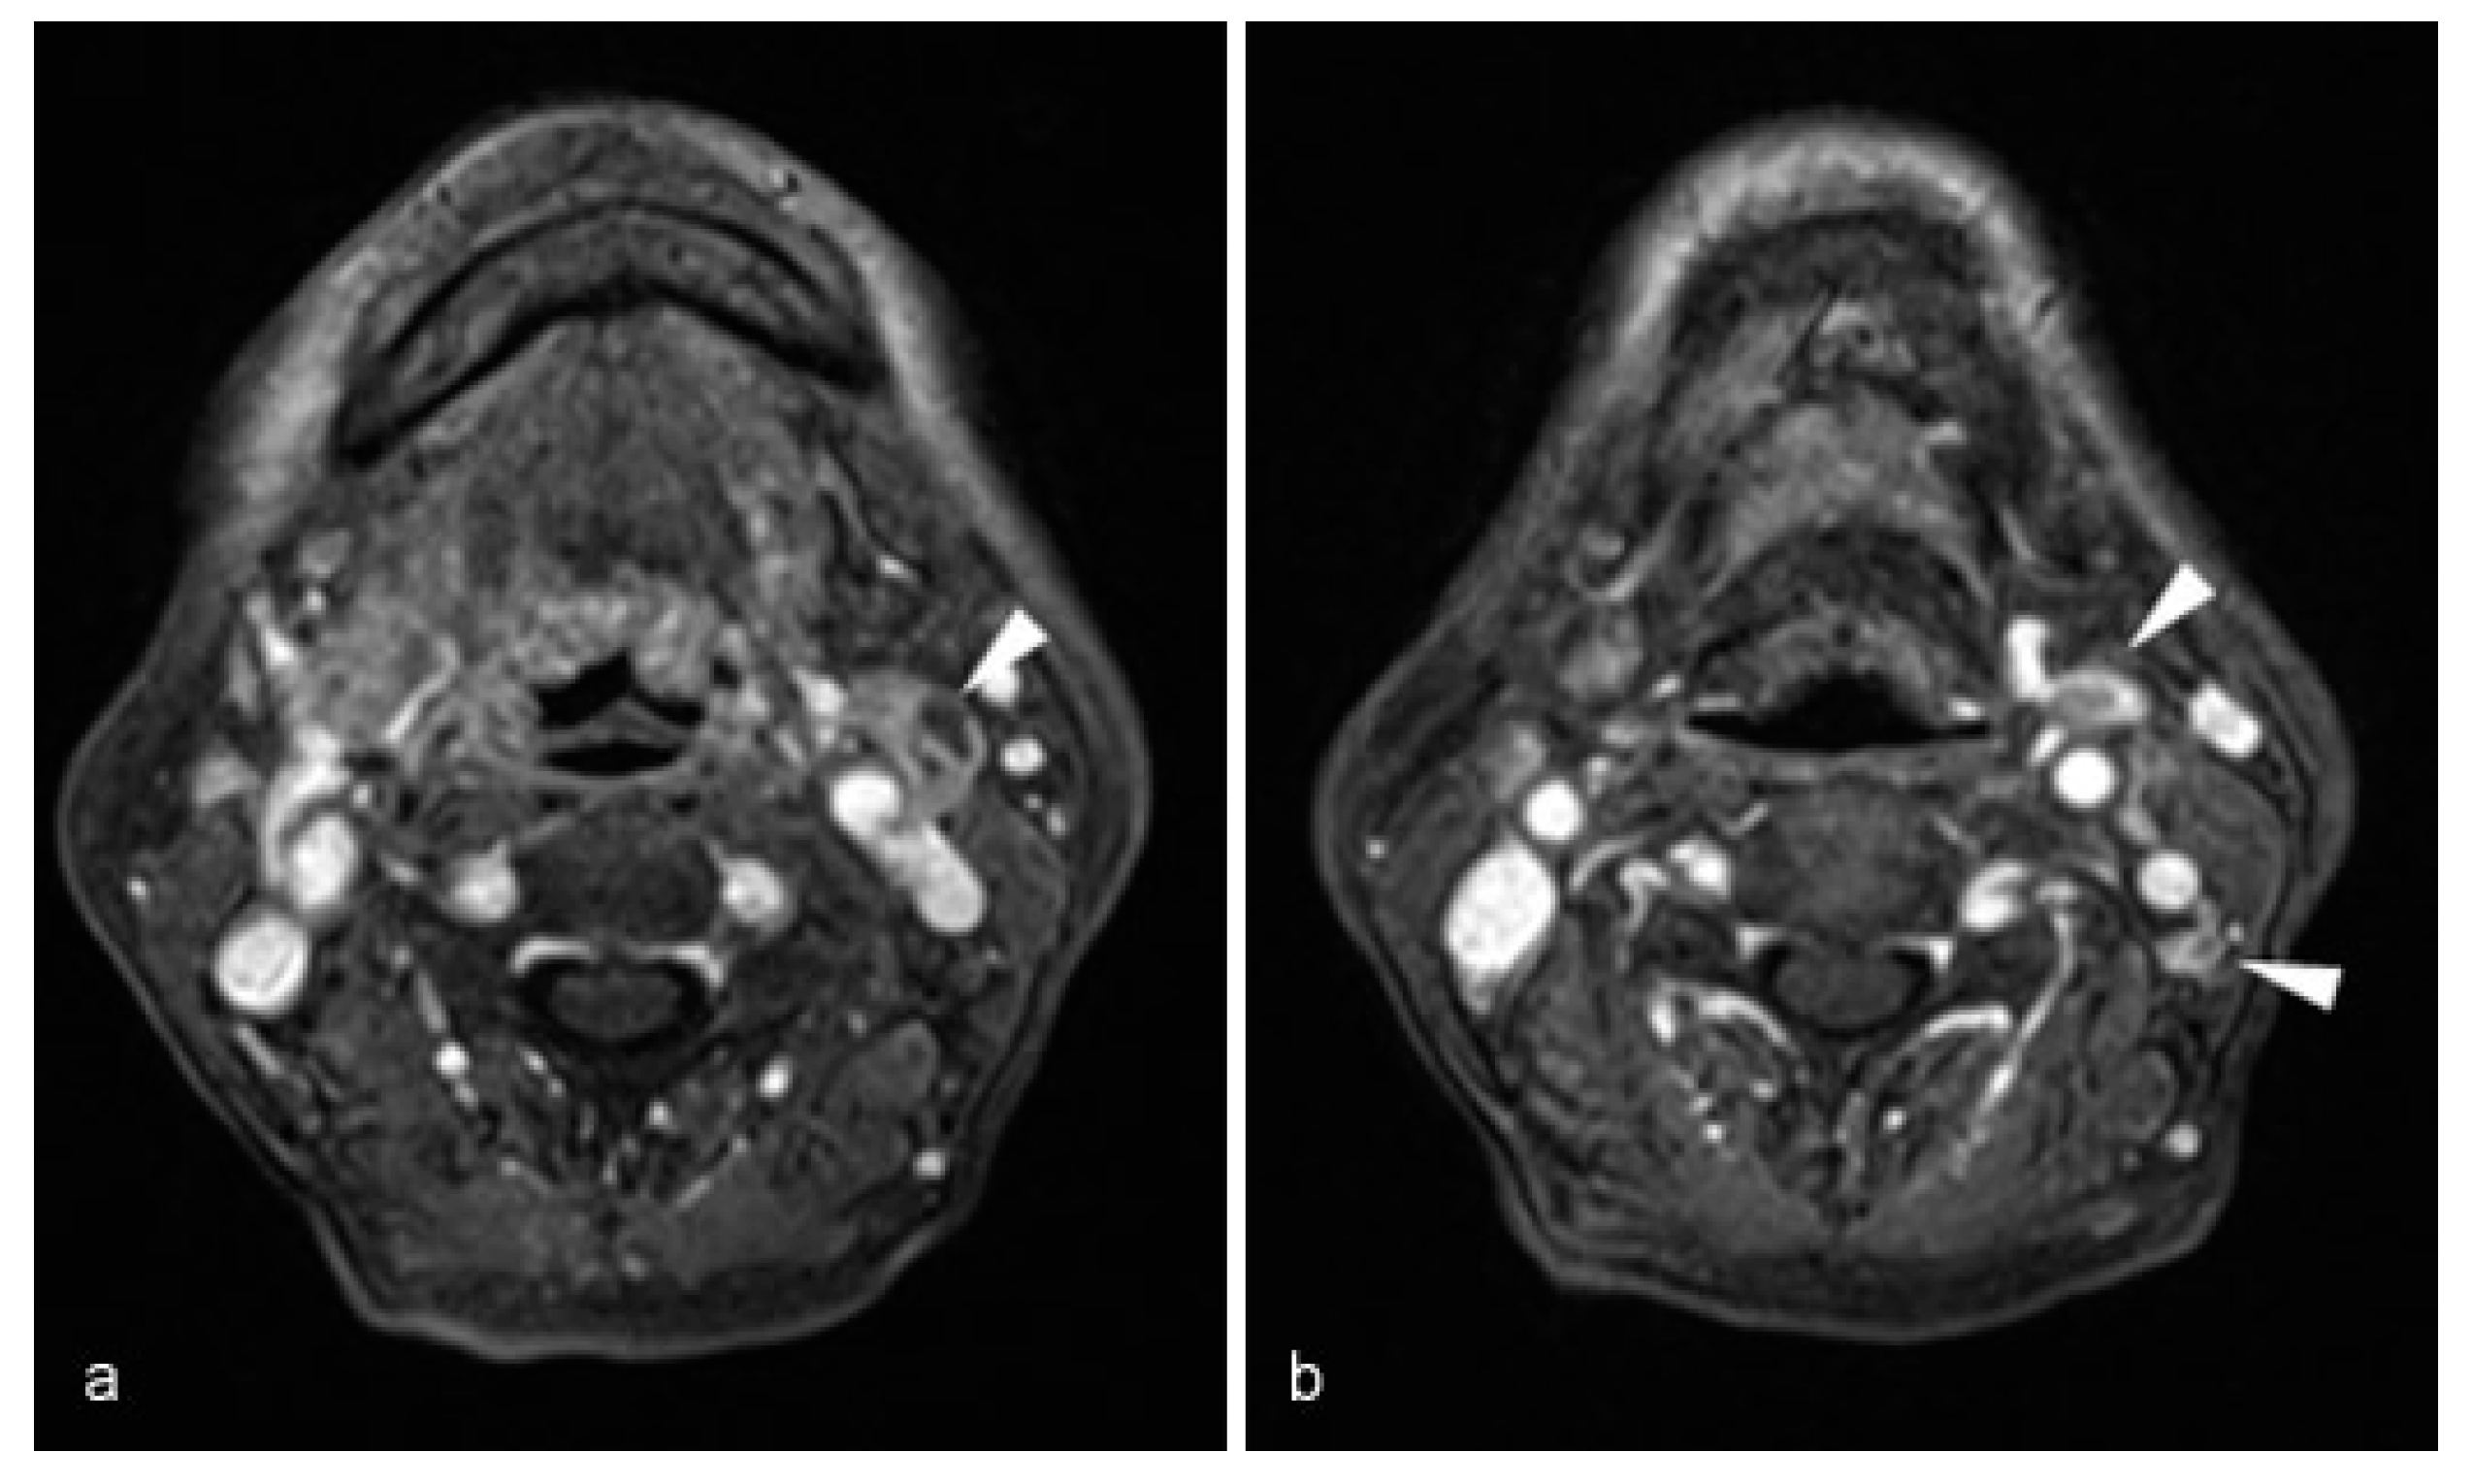

An 81-year-old Japanese woman with squamous cell carcinoma on the left side of the tongue was referred to our department. The tumor extended over a midline contralaterally and a swollen lymph node in Level IIA with fixation around soft tissue, which contrast-enhanced computed tomography (CT) showed, was palpable. The lesion was staged as cT3N1M0 according to the TNM Classification of Malignant Tumors (7th Edition, UICC) [6]. But there were two lymph nodes with an irregular contrast effect in Levels IIA and B in contrast-enhanced magnetic resonance imaging besides the obvious metastatic lymph node by contrast-enhanced CT that were suspected lymph node metastases (Figure 1). Therefore, RND, subtotal glossectomy, and simultaneous reconstruction using a PMMCF were performed. The PMMCF was elevated from the chest wall and moved upward. The clavicular periosteum around the pectoral branches of the thoracoacromial vessels was excised from the cervical and thoracic sides, and the periosteum on the inferior surface of the clavicle was detached and reflected to drop it downward [7,8]. The PMMCF was brought to the oral cavity via the subclavian route for reconstruction of the defect of the tongue (Figure 2).

Figure 1. Contrast-enhanced MRI (axial T1-weighted images, fat suppression, gadolinium enhancement) showed metastatic and metastases suspicious lymph node in Levels II A and B. (a) Fixed swollen lymph node detected contrast-enhanced CT (arrow head). (b) Two no swollen lymph nodes with irregular contrast effect (arrow head).